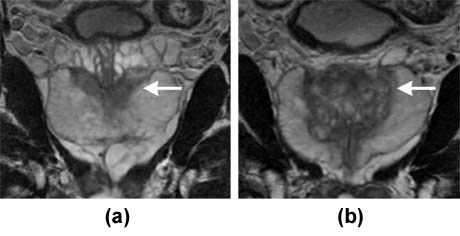

Imágenes por RMN ponderadas-T2 coronales que muestran una próstata normal. Las secciones representativas de la próstata muestran la zona central (a, (flecha)) y zona de transición (b, flecha)).

Nota: Las imágenes se muestra para fines ilustrativos. No trate de sacar conclusiones comparando esta imagen con otras en el sitio. Solamente los radiólogos calificados deben interpretar las imágenes.